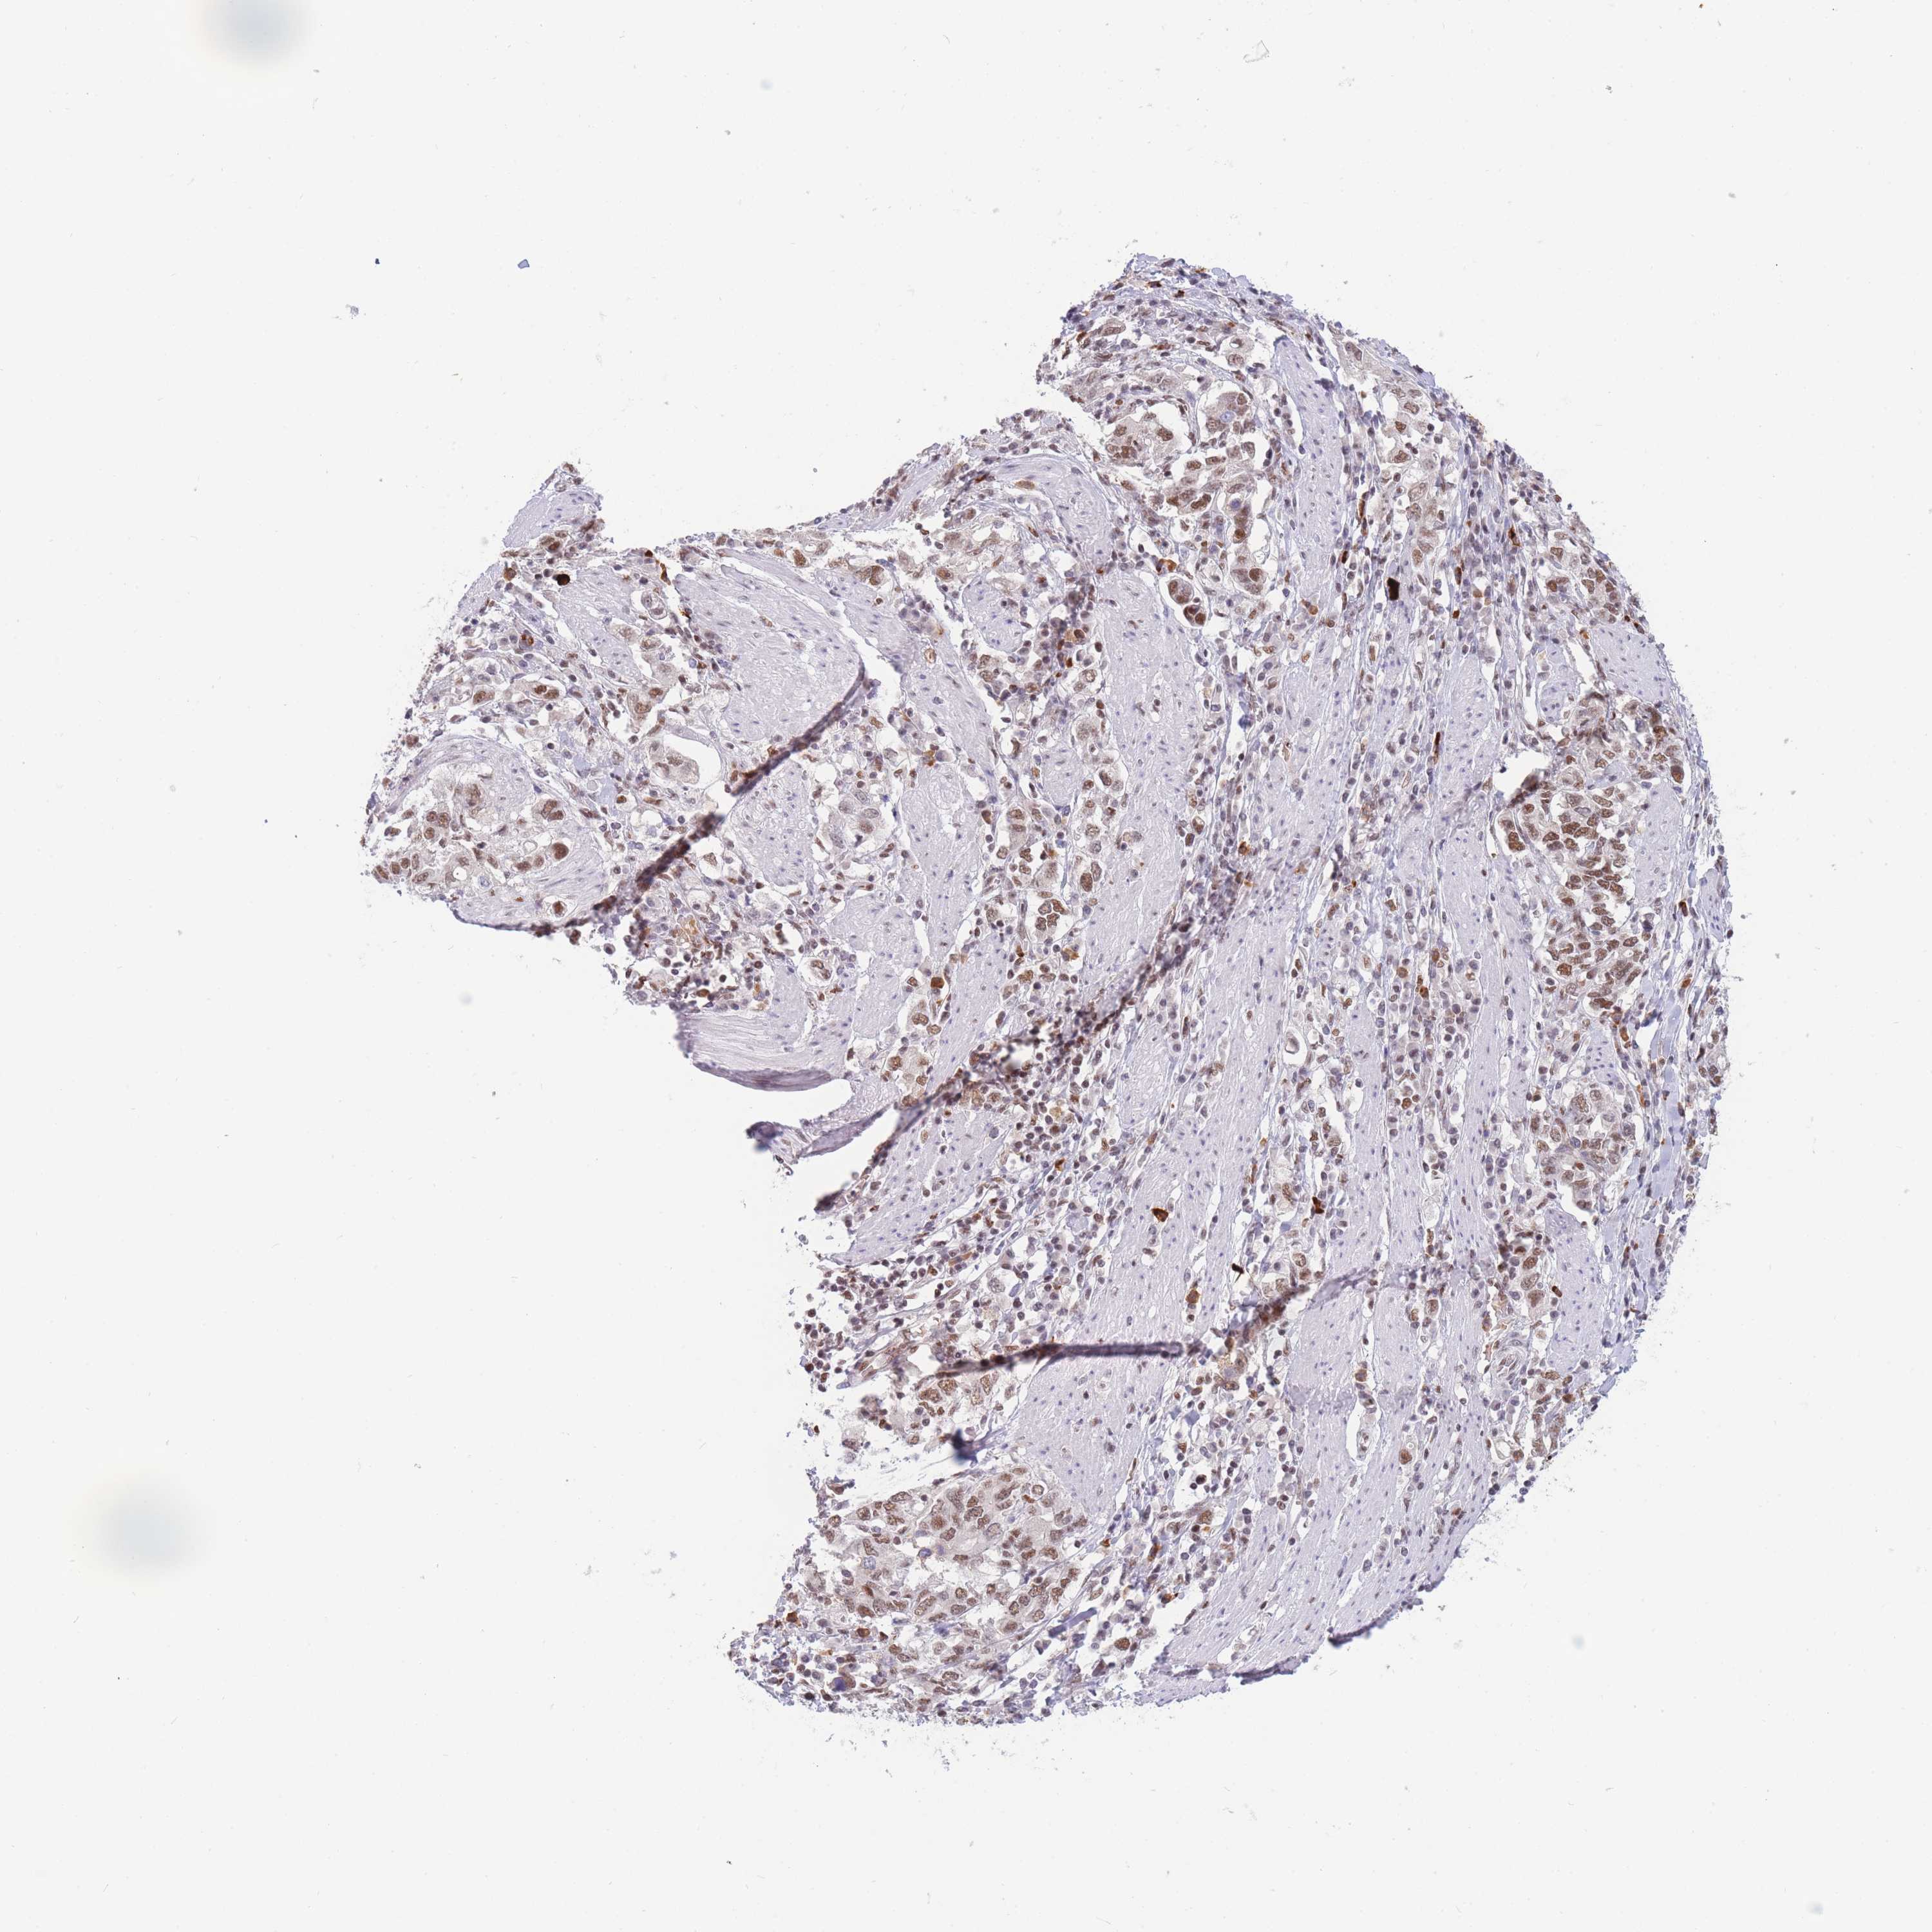

STOMACH CANCER - Protein expressioni

A mouse-over function shows sample information and annotation data. Click on an image to view it in a full screen mode. Samples can be filtered based on level of antibody staining by selecting one or several of the following categories: high, medium, low and not detected. The assay and annotation is described here.

Antibody stainingi

Antibody staining in the annotated cell types in the current human tissue is reported as not detected, low, medium, or high, based on conventional immunohistochemistry profiling in selected tissues. This score is based on the combination of the staining intensity and fraction of stained cells.

Each image is clickable and will lead to virtual microscopy that enables deeper exploration of all samples and also displays staining intensity scores, fraction scores and subcellular localization as well as patient and tissue information for each sample.

Antibody HPA031162

Antibody CAB009119

Staining

High

Medium

Low

Not detected

Intensity

Strong

Moderate

Weak

Negative

Quantity

>75%

75%-25%

<25%

None

Location

Nuclear

Cytoplasmic/membranous

Cytoplasmic/membranous,nuclear

Adenocarcinoma, NOS

Adenocarcinoma, High grade